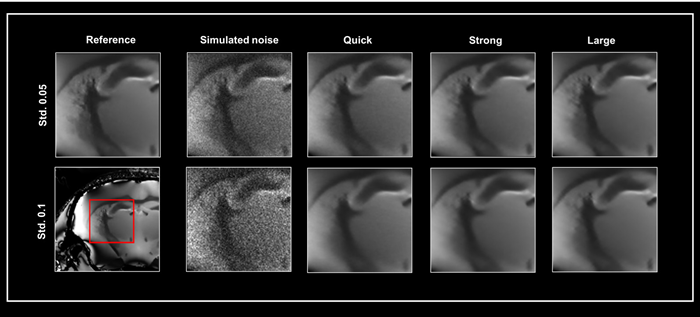

Fig 1 depicts exemplary denoising results for these three networks. A denoised 3D dataset was used as a reference to demonstrate the effect of denoising with different networks.

Two generated noise levels (standard deviation 0.05 and 0.1) were added to the reference image, which was then fed into the three denoising networks (Quick, Strong, and Large). All datasets were denoised with 50% pre-denoising and a denoising intensity of 100%.

Smart Noise Reduction using different neuronal networks

Figure 1. Smart Noise Reduction using different neuronal networks. A denoised 3D dataset was taken as ground truth (Reference) to which two varying levels of simulated noise were added, i.e. standard deviation (Std.) 0.05 and 0.1, respectively. Noisy data were subsequently reconstructed with the Quick, Strong, and Large networks. All data were denoised with a 100 % denoising level and 50 % pre-denoising. The area shown in the red box was selected for the similarity metrics in Table 1. Image Credit: Bruker BioSpin Group​​​​​​

To assess the quality of the rebuilt images presented in Fig 1. The Peak Signal to Noise Ratio (PSNR) and Structural SIMilarity (SSIM) indices between the reference image and the data reconstructed using the three different networks were computed (Table 1). The chosen area for analysis is highlighted in Fig 1.

While big networks provide the highest performance, quick reconstruction with Quick and Strong networks produces high-quality images.